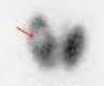

A

Pyramidal lobe uptake, suggestive of Graves disease

Note: The pyramidal lobe is seen in 10% of normal pts, but in 45% of Graves pts.